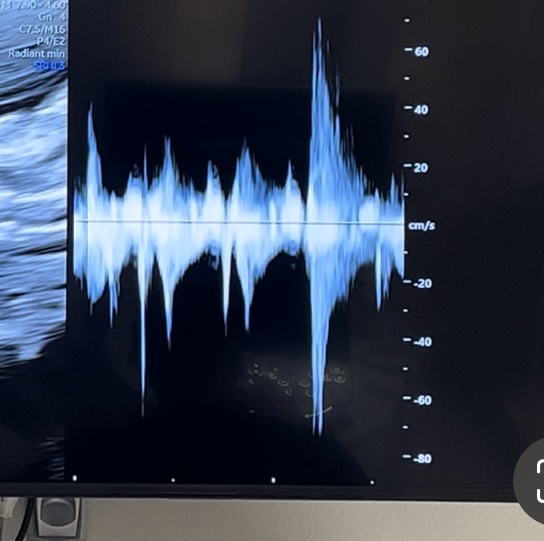

今日妊婦健診にいってきたのですが、エコー心拍確認の際に、いつも聞く心拍リズムとは異なっていることが気になりました。その時には気づかず、ドクターに直接聞くことができなかったのですが、自宅で動画を再度確認していて、リズムや、波形が少し乱れている気がして不安になってます。次の検診は3週間後なのですが、少し不安なので教えて欲しいです。

心拍エコーの際に、雑音がはいることは可能性としてありますか?

波形が乱れる可能性もありますか?

実際に一緒に聴取しているわけではないので、わからないのですが、ドップラーで聴取をしていると、雑音のようなものが入ることもありますよ。

心拍を見ようとした部位によっては、波形も乱れやすかったりすることはあるのではないかなとも思いました。